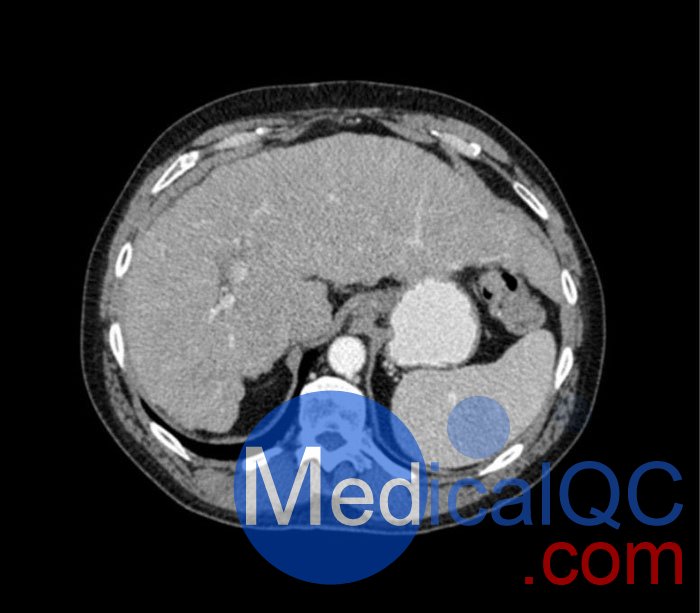

WEK53-04肝硬化腹部模體,WEK53-04腹部模體代表膽囊切除術(shù)后的腹部,帶有小夾子。肝臟有肝硬化的典型體征,在第三腰椎水平植入下腔靜脈過濾器。兩個腎臟都有囊性病變,左側(cè)有一小塊腎結(jié)石。

真實模擬脈管系統(tǒng)、骨骼和軟組織,包括肝臟、胰腺、脾臟、腎上腺、腎臟、胃、小腸和結(jié)腸。

• 肝硬化

• 膽囊切除術(shù)

• 腎囊腫